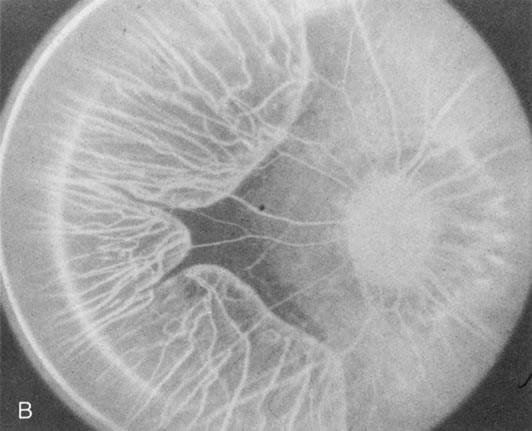

When the macula has typical superficial linear plications radiating from the fovea seen with schisis (e.g., juvenile retinoschisis, Goldmann-Favre disease), FA is normal (Fig. 8A and B). This indicates that the pathology is in the inner retina (probably Henle's fiber layer, considering the spokewheel pattern). However, when the schisis flattens, it is not uncommon to see a transmitted hyperfluorescence suggesting a secondary atrophy to the RPE (Fig. 8C and D).

Fig. 8. Juvenile XLR retinoschisis. The superficial macula schisis (A) does not affect the angiogram (B) except in a few areas where it has flattened and resulted in some pigment dispersion. When the macular schisis has entirely flattened (C) there is a mild transmission hyperfluorescence (D). At this stage the diagnosis can be suspected by the presence of an inferior retinoschisis (present in half) and confirmed by the typical electroretinographic finding of a scotopic electronegative response (present in all affected males).

The periphery may show schisis or vascular sheathing. Histopathology of the peripheral schisis in juvenile retinoschisis documents a splitting of the nerve fiber layer.13 FA shows retinal vascular abnormalities, including capillary nonperfusion, focal and diffuse vascular leakage, and intraretinal neovascularization, in many of these disorders.14 These may or may not be associated with schisis.

As with generalized tapetoretinal dystrophy (RP), FA clearly delineates retinal vascular decompensation in some of these patients. What remains to be answered is whether this is part of the basic disease process or a secondary reaction to it.